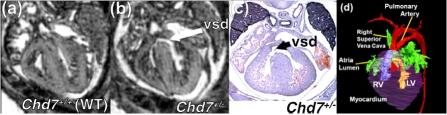

Cardiovascular magnetic resonance (CMR) imaging is the modality of choice for clinical studies of the heart and vasculature, offering detailed images of both structure and function with high temporal resolution.Small animals are increasingly used for genetic and translational research, in conjunction with models of common pathologies such as myocardial infarction. In all cases, effective methods for characterising a wide range of functional and anatomical parameters are crucial for robust studies.CMR is the gold-standard for the non-invasive examination of these models, although physiological differences, such as rapid heart rate, make this a greater challenge than conventional clinical imaging. However, with the help of specialised magnetic resonance (MR) systems, novel gating strategies and optimised pulse sequences, high-quality images can be obtained in these animals despite their small size. In this review, we provide an overview of the principal CMR techniques for small animals for example cine, angiography and perfusion imaging, which can provide measures such as ejection fraction, vessel anatomy and local blood flow, respectively. In combination with MR contrast agents, regional dysfunction in the heart can also be identified and assessed. We also discuss optimal methods for analysing CMR data, particularly the use of semi-automated tools for parameter measurement to reduce analysis time. Finally, we describe current and emerging methods for imaging the developing heart, aiding characterisation of congenital cardiovascular defects. Advanced small animal CMR now offers an unparalleled range of cardiovascular assessments. Employing these methods should allow new insights into the structural, functional and molecular basis of the cardiovascular system.

心血管磁共振(CMR)成像技术是心脏和血管临床研究的首选方式,能够以高时间分辨率提供心脏结构和功能的详细图像。越来越多的小动物被用于基因和转化研究,并与诸如心肌梗死等常见病理模型相结合。在所有情况下,有效表征各种功能和解剖参数的方法对于可靠的研究至关重要。CMR是这些模型无创检查的金标准,尽管诸如心率过快等生理差异使得这项工作比传统临床成像更具挑战性。然而,借助专门的磁共振(MR)系统、新颖的门控策略和优化的脉冲序列,尽管动物体型小,仍可在这些动物身上获得高质量图像。在本综述中,我们概述了用于小动物的主要CMR技术,例如电影成像、血管造影和灌注成像,它们可分别提供诸如射血分数、血管解剖结构和局部血流等测量值。结合MR造影剂,还可识别和评估心脏局部功能障碍。我们还讨论了分析CMR数据的最佳方法,特别是使用半自动工具进行参数测量以减少分析时间。最后,我们描述了当前和新兴的用于发育中心脏成像的方法,有助于先天性心血管缺陷的特征描述。先进的小动物CMR现在提供了无与伦比的一系列心血管评估。采用这些方法应该能够对心血管系统的结构、功能和分子基础有新的认识。